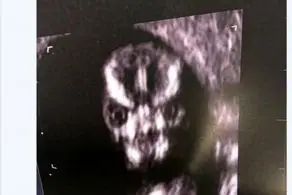

علامت جنجالی یک جنین با دستش در سونوگرافی! + عکس

کودکی که قبل از تولدش معروف شد، مادر این کودک که برای اسکن و اطمینان از سلامتی جنین به بیمارستان رفته بود با صحنه عجیبی مواجه شد، لحظه ای که جنین انگشتان خود را به علامت پیروزی بالا گرفته بود.

به گزارش منیبان؛ جنینی که در شکم مادر هنگام گرفتن سونو علامت پیروزی نشان داده است،مادر این کودک که برای اسکن و اطمینان از سلامتی جنین به بیمارستان رفته بود با صحنه عجیبی مواجه شد ،جنین انگشتان خود را به علامت پیروزی بالا گرفته بود جالب اینجاست که این جنین 20 هفته بیشتر ندارد. مادر 35 ساله (ماری باسول) این جنین گفته وقتی که این صحنه را در بیمارستان منچستر دیده نمیتوانسته جلوی خنده خود را بگیرد، این زوج اهل گدالمینگ انگلیس هستند.